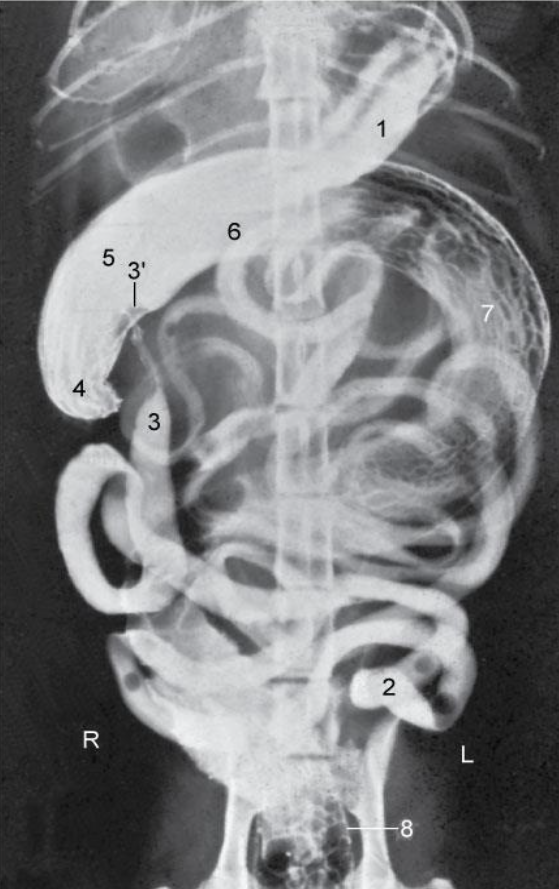

Re. 3 regions of colon. topography?

ascending colon - right side

transverse - colon cranial to the root of mesentery (right side)

descending colon - left side

Re. rectum. topography?

Begins at the pelvic inlet continuous with descending colon